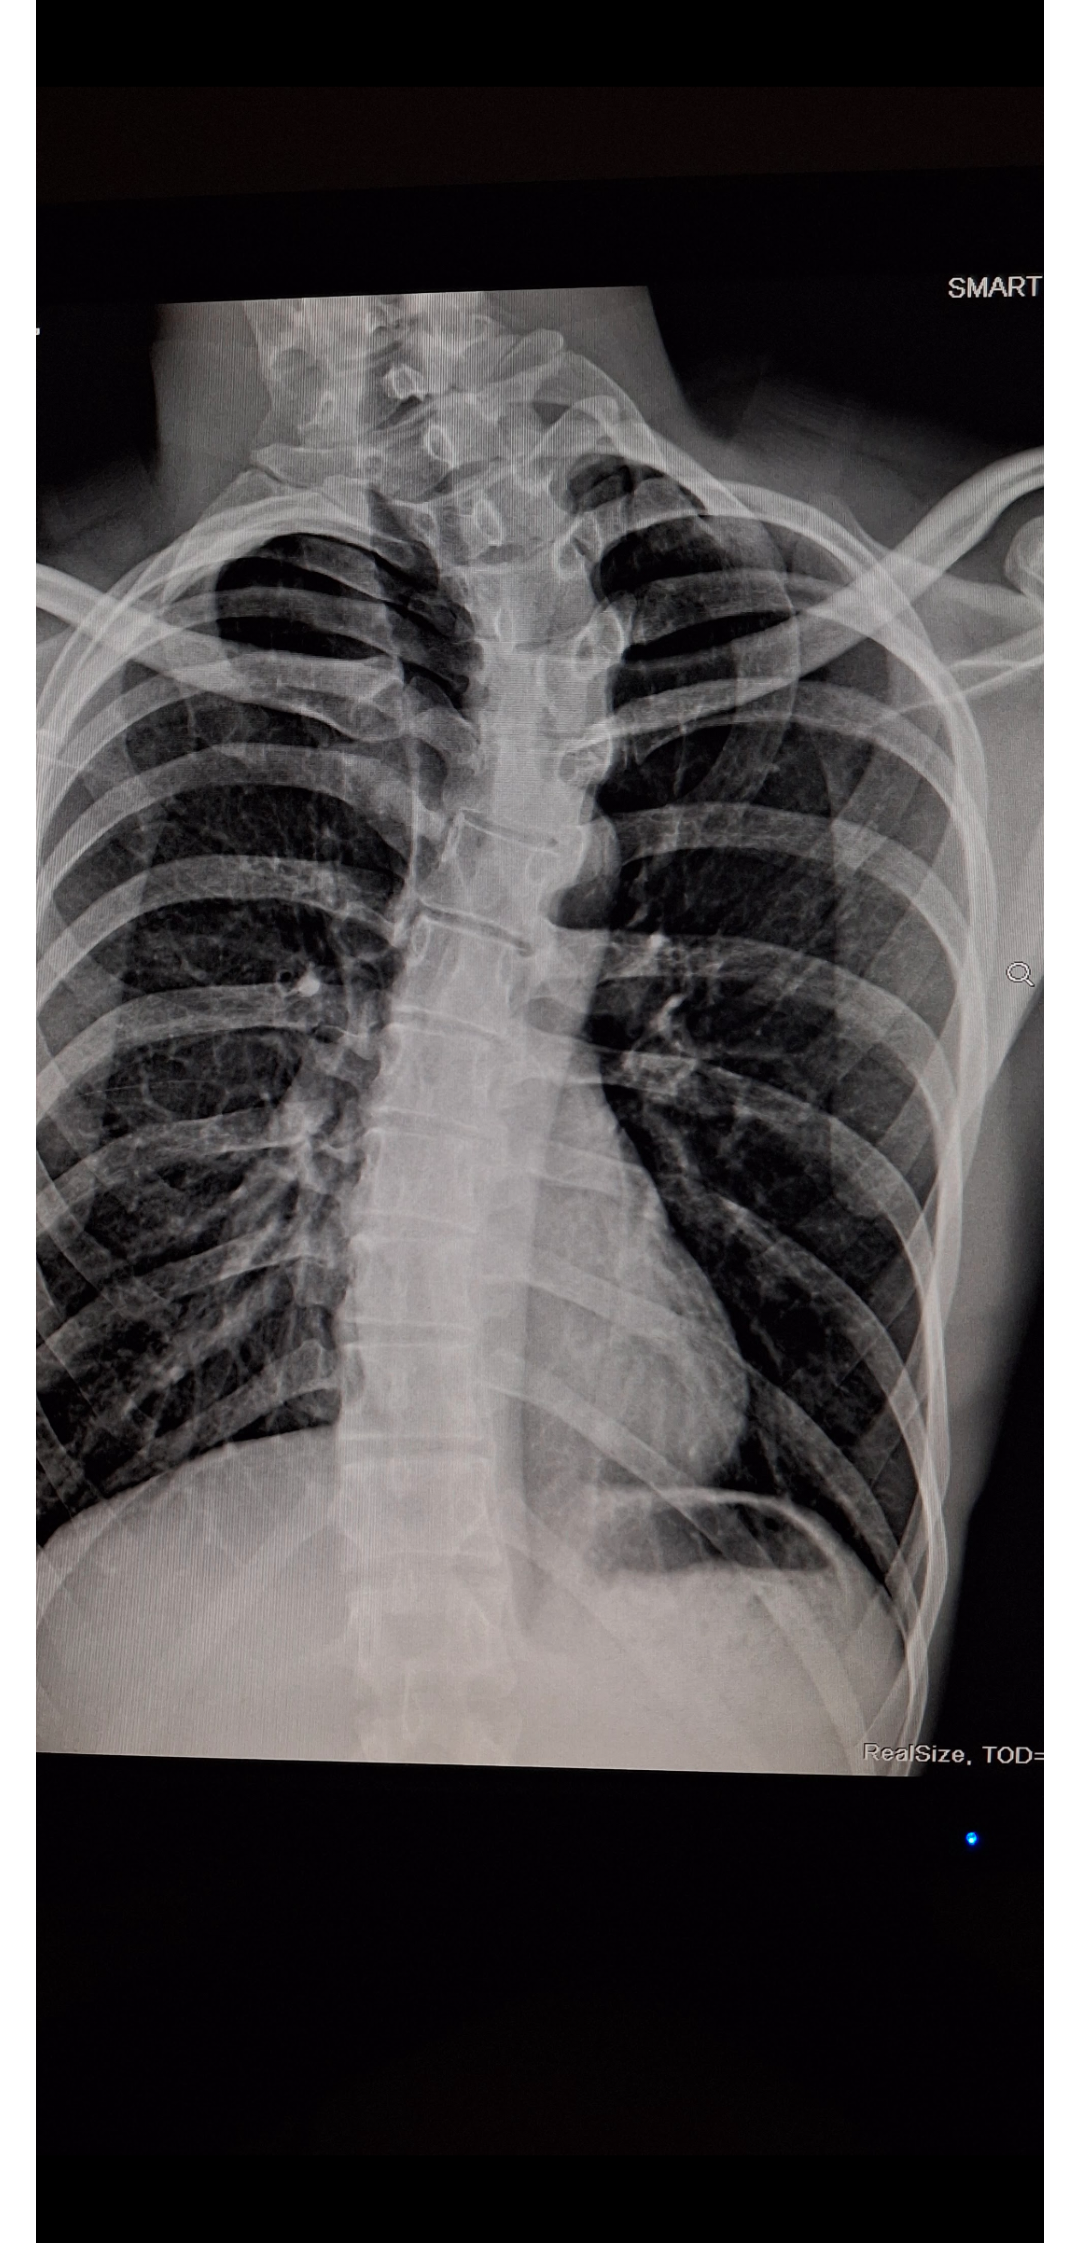

“Just had a lung checkup and found out I was born bent.”

Kurdonoid/Reddit

When you go for a routine check and suddenly realize you’ve been assembled with a plot twist. That x-ray is definitely not what I expected to see. Guess I can finally say I have character — and my spine has all the personality.